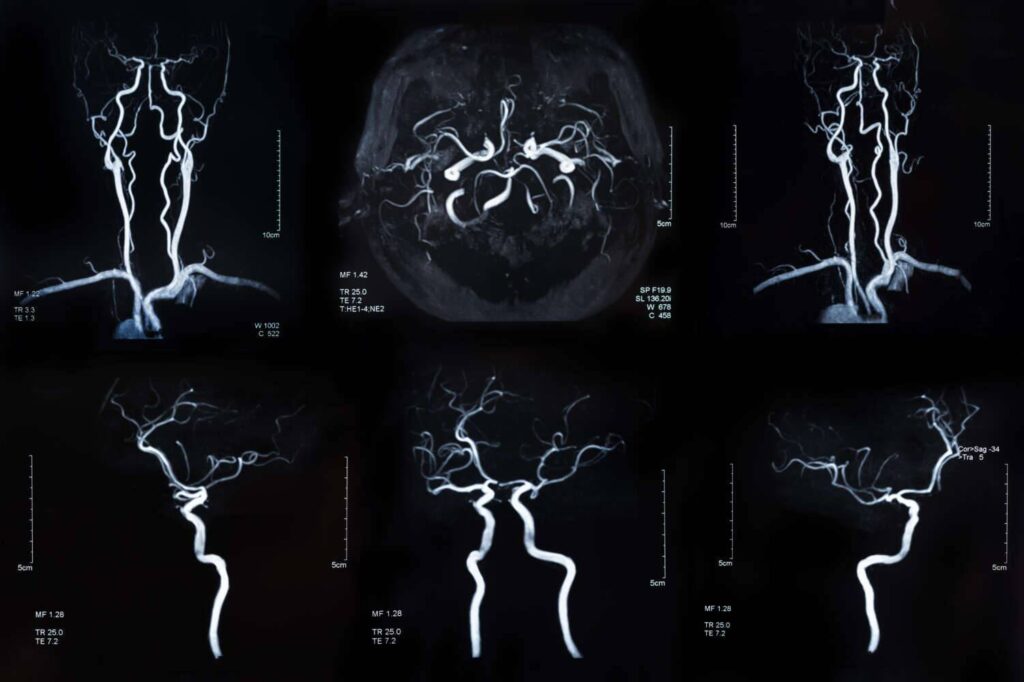

Die MRT-Angiographie basiert prinzipiell auf der Methode der Magnetresonanztomographie (MRT). Es werden also gänzlich ohne den Einsatz von Röntgenstrahlung Schnittbilder des Körperinneren mittels starker Magnetfelder und Radiowellen angefertigt. Diese zweidimensionalen Bilder können anschließend am Computer übereinandergelegt werden, wodurch ein dreidimensionaler Eindruck entsteht. Bei der MRT -Angiographie liegt dabei allerdings der besondere Fokus auf den Blutgefäßen.

Da die MRT eine hochpräzise Untersuchungstechnik ist, lassen sich so bereits kleinste Veränderungen sicher erkennen. Zusätzlich kann durch eine computergestützte Bildsubtraktion anschließend auch ein 3D-Datensatz erzeugt werden, welcher nur noch die Gefäße enthält. So können diese isoliert vom Rest des Körpers bis ins letzte Detail unter die Lupe genommen werden.

Doch auch eine Gefäßdarstellung gänzlich ohne Kontrastmittel ist inzwischen möglich. Die am weitesten verbreitete Methode hierfür ist die sogenannte „Time-of-flight“-MRT-Angiographie (TOF-MRA). Dabei nutzt man aus, dass das gerade einfließende Blut eine deutlich größere Magnetisierung aufweist als das partiell gesättigte umliegende Gewebe und damit auf den MRT-Bildern heller erscheint.

Entscheidend ist dabei allerdings, dass die Aufnahmeebene der MRA senkrecht zu den darstellenden Blutgefäßen ausgerichtet ist, damit immer wieder ungesättigtes Blut in die Messschicht einfließt und so der Kontrast sichtbar gemacht werden kann. Allerdings können Atembewegung bei diesem Verfahren besonders störend sein, weshalb sich die TOF-MRA insbesondere bei der Darstellung der intrakraniellen Gefäße bewährt hat.